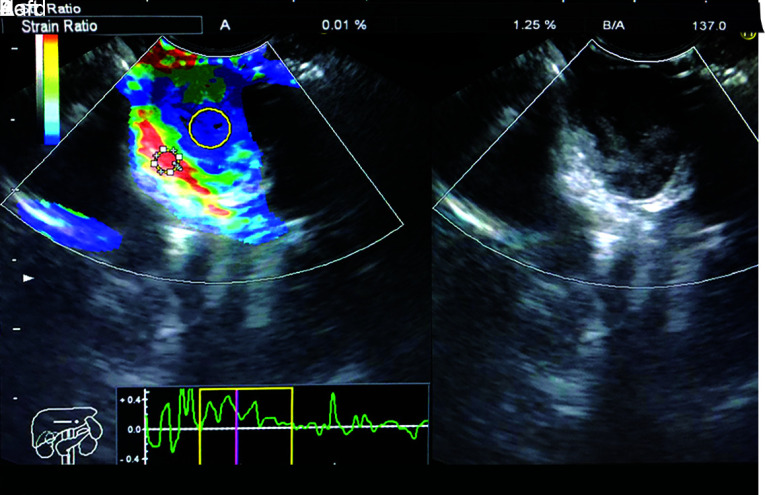

Materials and methods: Twenty-three lesions with histopathological diagnoses of 13 GISTs and 10 leiomyomas were evaluated. The lesions' SR values were obtained from EUS reports retrospectively. Giovannini's classification was performed according to the elastography images recorded in the system. The effectiveness of SR and Gc in the distinction between GIST and leiomyomas was evaluated.

Results: Twelve of the GISTs and 3 of the leiomyomas were with scores 4 and 5 according to Gc (p = 0.006). Gastrointestinal stromal tumors had a higher SR than leiomyomas (p = 0.001). For the diagnosis of GISTs, sensitivity/specificity/diagnostic accuracy were 92.3%/80%/87% for SR alone, 92.3%/70%/82.6% for Gc alone, and 84.6%/80%/82.6% for the use of both SR and Gc.